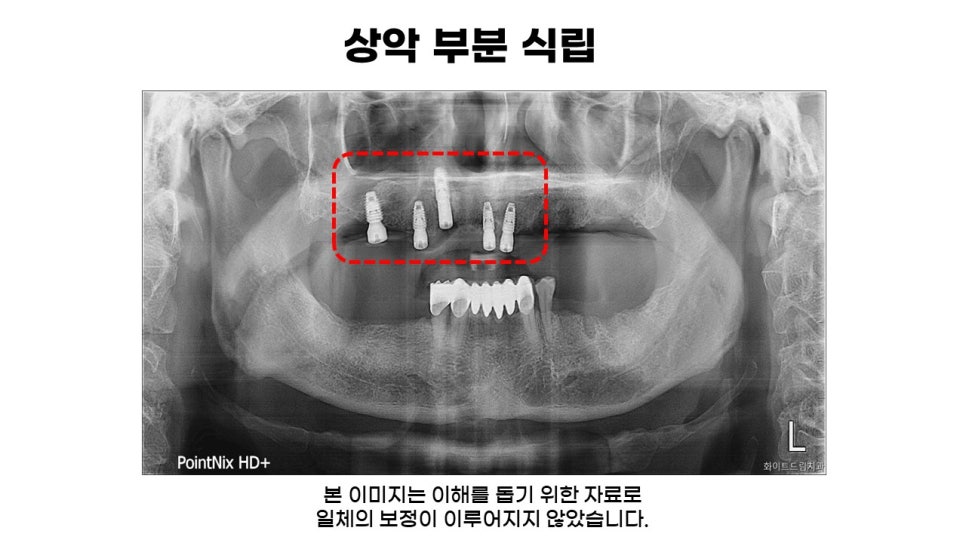

다음은 필요한 부위에만 임플란트 보철물을 식립한 모습입니다.

상악 8개와 하악 4개, 총 12개의 보철물을 식립해드렸는데요. 상악은 디오임플란트를 사용하여 3D스캐너와 CT로 골조직, 주변 치아와의 거리와 각도 신경 위치 등을 파아가여 진행해드렸습니다.

또한, 풀케이스는 상, 하악의 교합이 중요하고 정밀한 진단을 해드리는 것이 중요하므로 오차를 줄이기 위해 디지털 시스템으로 모의 수술을 함께 진행해드렸습니다.

앞서 말씀드린대로 하악 구치부 송곳니는 잇몸 치료를 통해 치아개선이 가능하고 남아있는 뼈의 양이 충분한 상태이셨는데요. 빠른 회복을 위해 발치하지 않고 임플란트 나사가 알맞은 각도로 식립된 모습을 확인할 수 있습니다.

환자분의 구강 상태를 면밀하게 살펴보니, 상악동 치조골 두께가 3~4mm 정도이셨는데요.

상악동 막부분이 찢어지거나 염증이 생겨 임플란트 픽스처가 흔들리지 않도록 상악동 거상술 및 치조골 이식을 하여 임플란트를 심을 수 있도록 도와드렸습니다.

무리해서 임플란트를 심는 경우 추후 발생할 수 있는 문제가 많기 떄문에 상악의 경우 치조골이 5mm 이하이면 환자분들께 알맞은 방법으로 이식술을 권해드리고 있습니다.